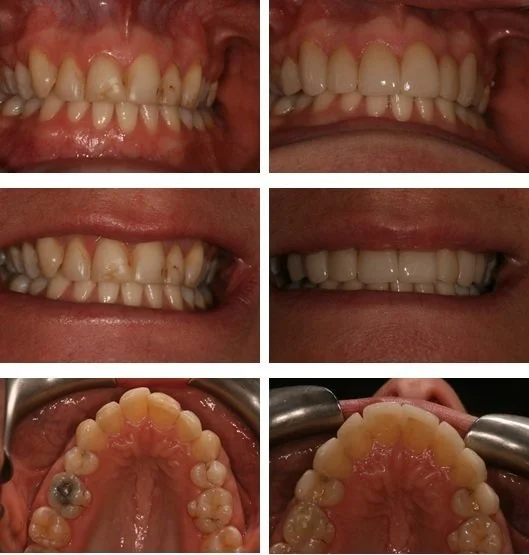

Case 1 (Refer to images below)

This lovely patient attended Aesthetic Dental Zone for a Smile Makeover. She had suffered an unfortunate accident which caused devastating trauma to her upper front teeth. As you can see from the images it was very traumatising for her at such a young age to have damaged her front teeth this way.

Allowing a period of approximately two months after the Root Canal Treatment we were able to fit her fully porcelain permanent veneers.

This incredibly brave and lovely lady is extremely happy with the outcome and we are so pleased we were able to help her smile proudly.

Smile Design Before & After